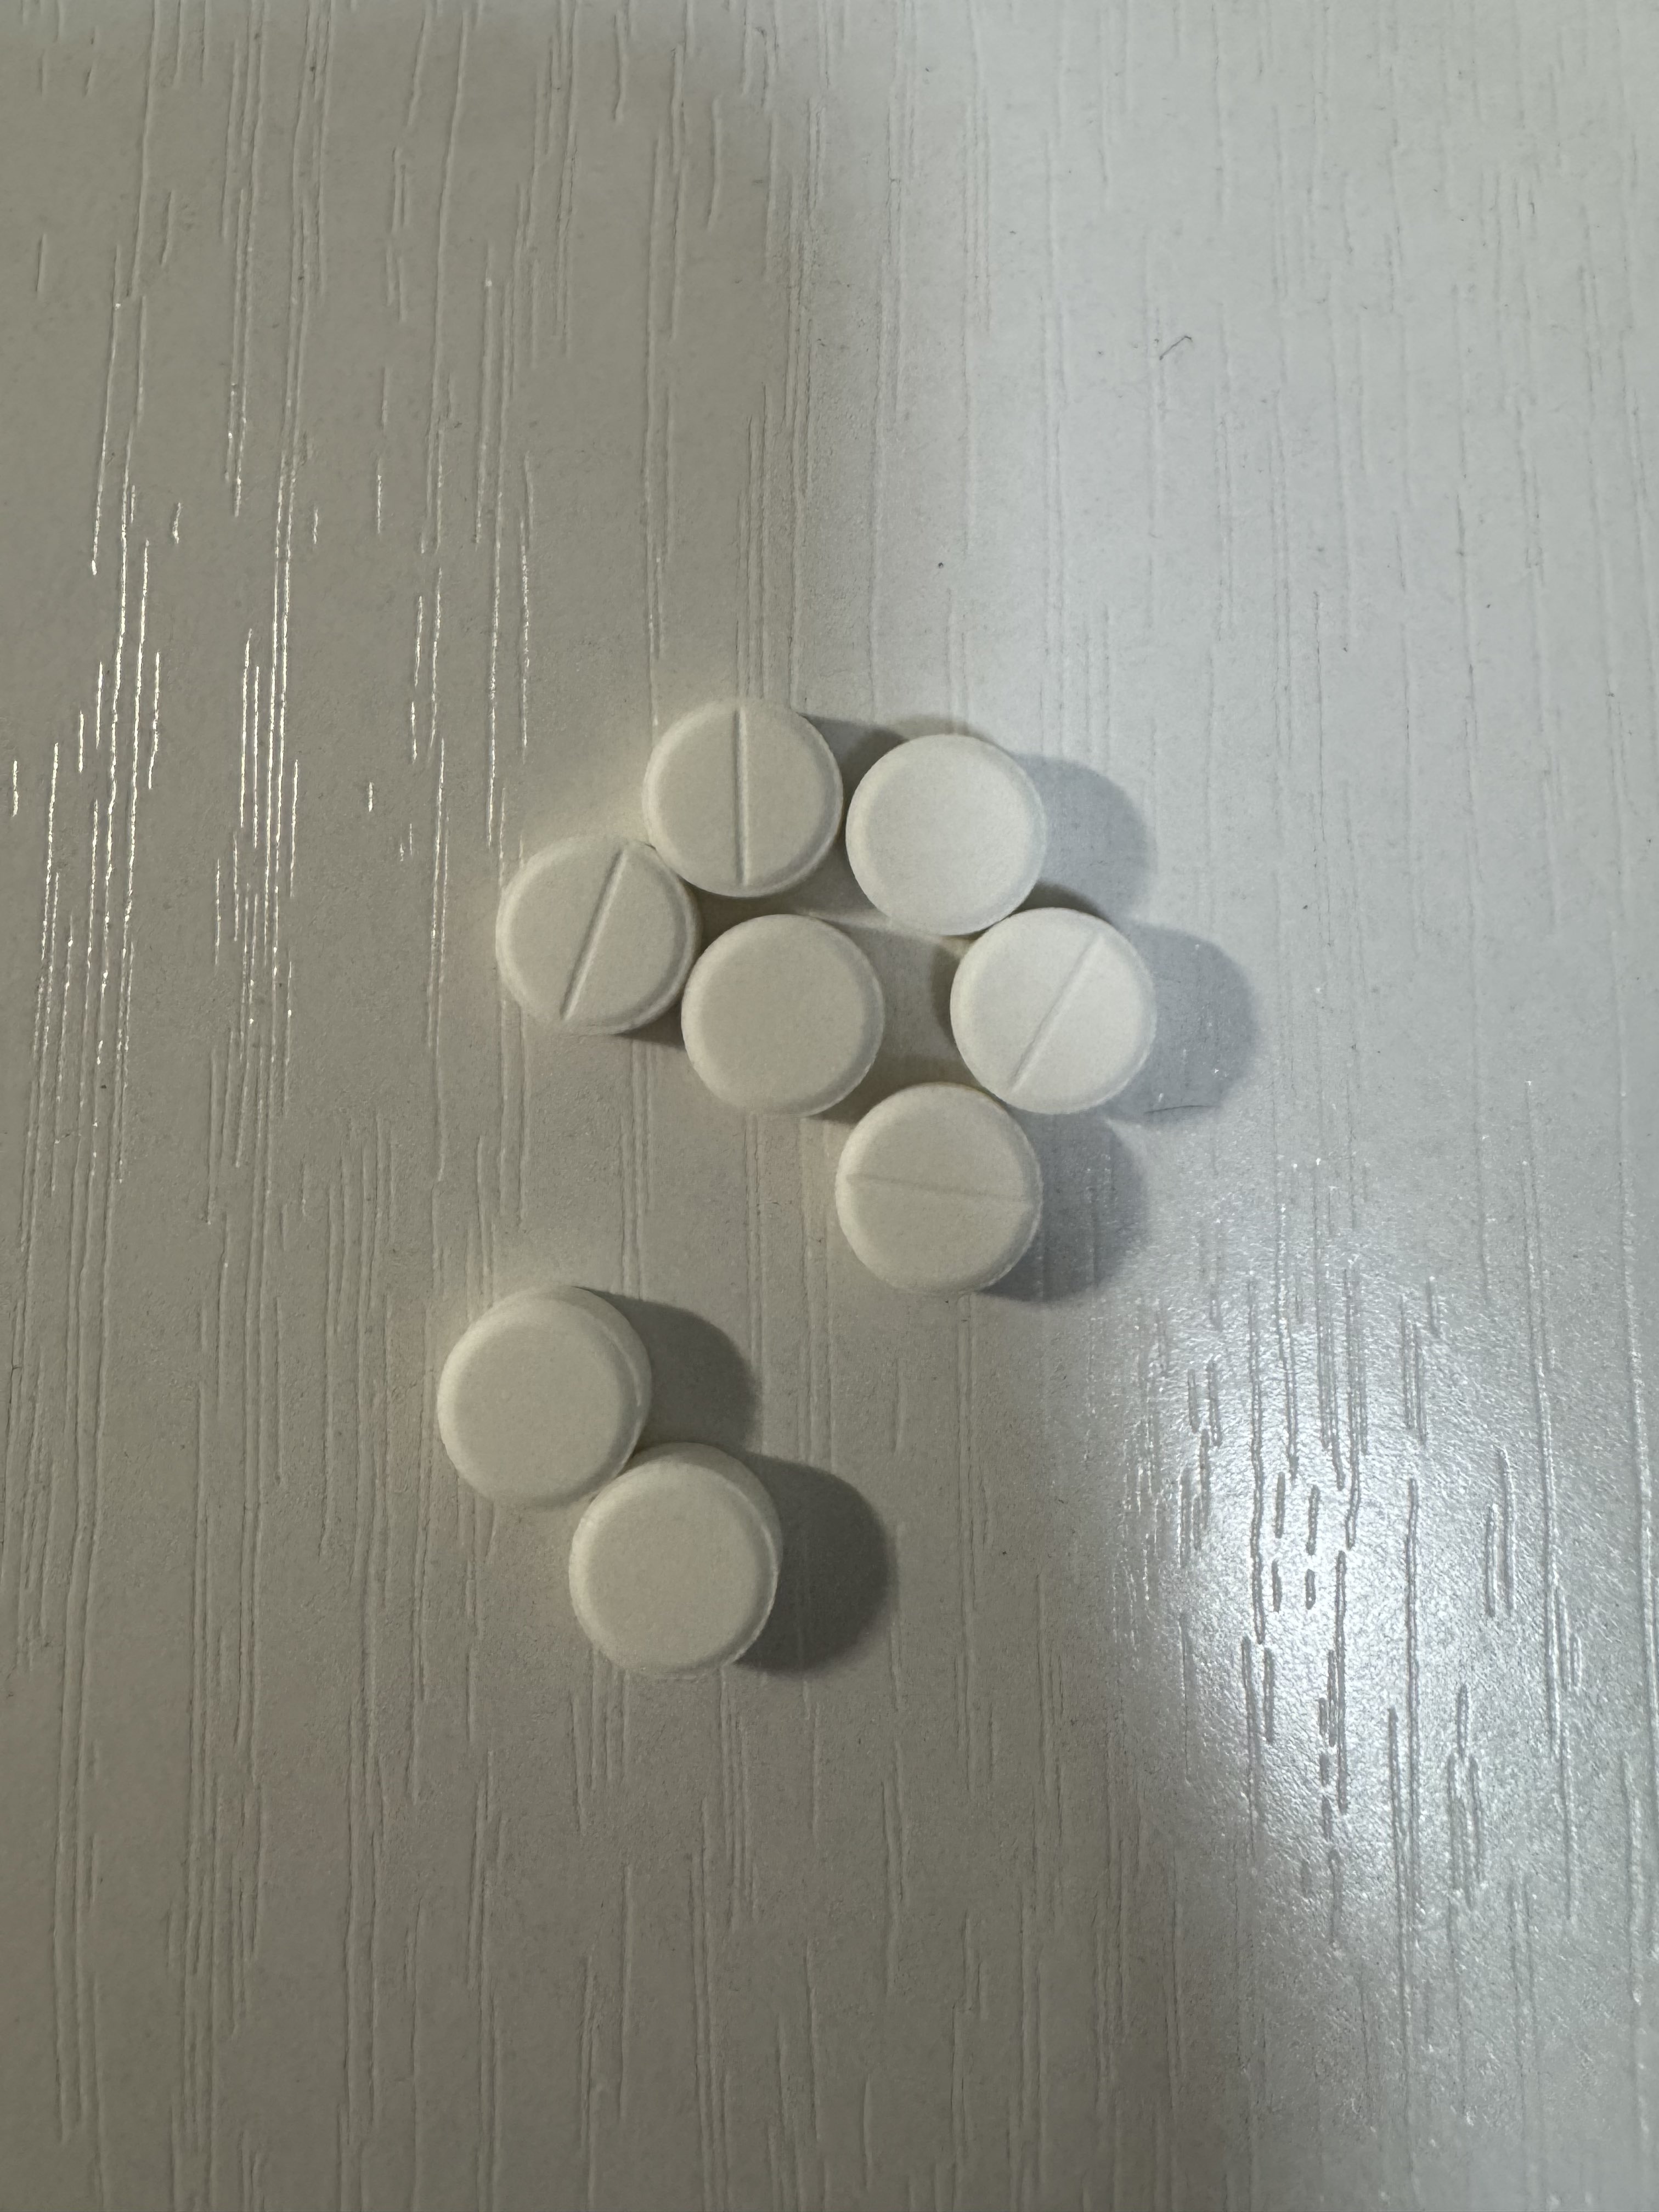

一些白兔27t的体验:

显著的梦境增强,几乎是半梦半醒的状态(或许是咖啡因导致的?),会梦到很多开心的事态发展并相信那就是事实,虽然在6h的睡眠后醒来不记得内容了(好希望能记住)

没有服用会干扰酶的药物或食物。

睡眠期间心率和血氧的数据比平时低一些。总之没有发生什么很特别的事。 https://t.co/PAXqkakGGo